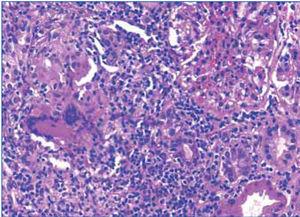

A cervical adenopathy biopsy was performed in which epithelioid granulomatous inflammation was observed with extensive caseous necrosis (Figure 1). A few bacilli were observed in the Ziehl-Nielsen stain (Figure 2).

Given the clinical (severe renal failure), radiological (kidneys of normal size and echostructure) and laboratory findings (anaemia, proteinuria and microscopic haematuria), a renal biopsy was performed in which interstitial inflammation at the expense of lymphocytes was detected, accompanied by histiocytes, which formed granulomas at several points (Figure 2 and 3). One of these contained multinucleated Langhans giant cells. Glomeruli were normal. Granular material occupied the tubules and the epithelium was flattened. There were no microorganisms in the PAS or Ziehl-Nielsen stain.

Figure 1. Extensive caseous necrosis foci in the right supraclavicular lymph node biopsy

Figure 2. Detection of a bacillus in the Ziehl-Nielsen stain of the lymph node biopsy

Figure 3. Interstitial lymphocytic infiltrate and epithelioid granuloma in the renal biopsy

Figure 4. Detail of the interstitial infiltrate